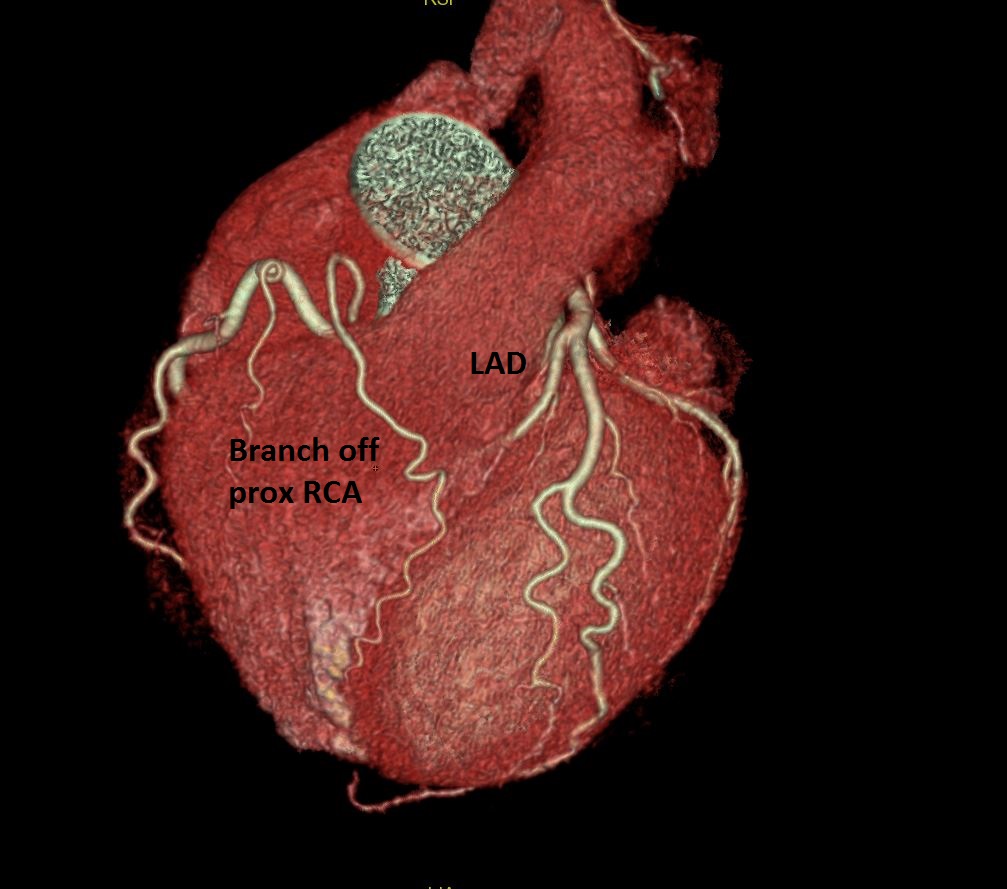

Nice example of a sort of Type IV LAD #YesCCT short LAD which becomes a septal branch with a branch off the prox RCA coursing anterior to the RVOT to the anterior interventricular groove @Heart_SCCT